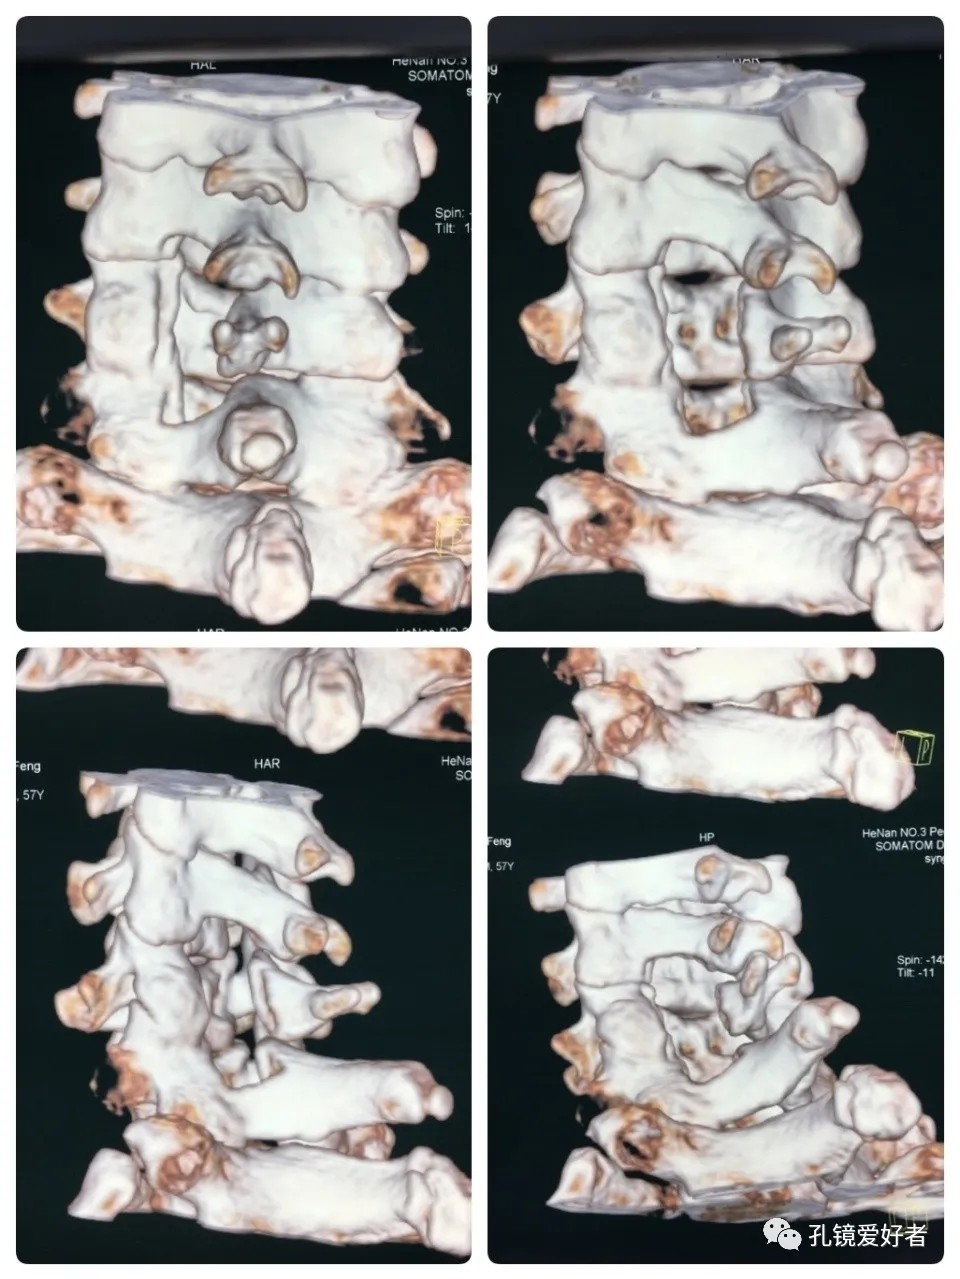

CT Imaging of 3D Reconstruction